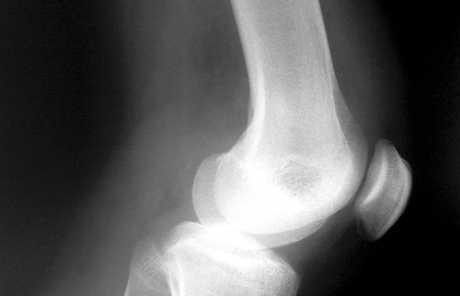

Hrskavica na pateli

Brušenje neravnina na pateli rutinski je zahvat koji se izvodi metodom artroskopije. Postoperativni oporavak relativno je brz, a uključuje metode fizioterapije i kineziterapije